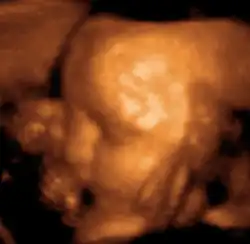

Ultradźwięki znajdują także zastosowanie w medycynie. Za pomocą urządzenia generującego i rejestrującego fale ultradźwiękowe (ultrasonograf) można uzyskać obraz narządów wewnętrznych. Fale dźwiękowe znalazły szerokie zastosowanie np. w stomatologii do tzw. skalingu, tj. ultradźwiękowego usuwania kamienia nazębnego.